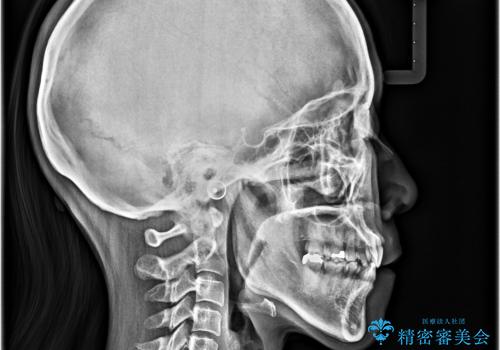

抜歯矯正 ワイヤー装置で横顔の印象を改善

- 前歯のデコボコと口元の突出感を気にして来院された患者様です。

上下前歯がくちばしのように突出していたため、上下左右の第一小臼歯4本を抜歯し、ワイヤー装置にて矯正治療を行うこととしました。

上顎骨に対して下顎骨がやや前方位に位置しているため、歯肉退縮を回避するために下顎前歯をあまり内側に移動させることができない状況でしたが、十分に口元の突出感を改善することができました。